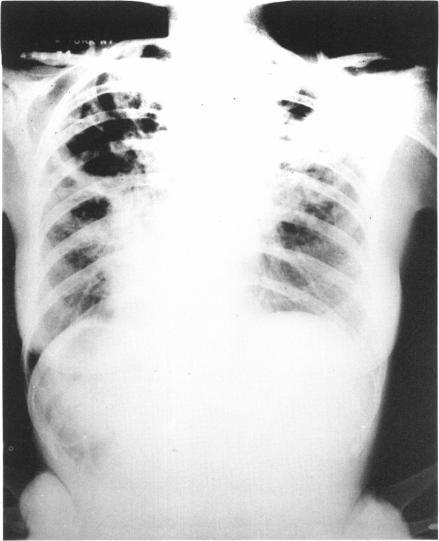

Pulmonary tuberculosis: evolution of modern therapy.

Bull N Y Acad Med. 1973 Mar;49(3):163-96.